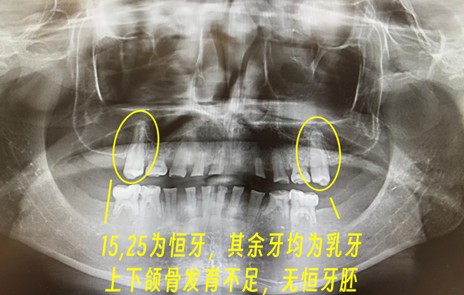

先天缺牙的诊断本身并不复杂。CBCT影像下,牙胚缺失一目了然。真正的挑战在于:如何在颌骨持续发育的背景下,制定一套能够伴随患者成长的修复方案。

小文(化名)的特殊性在于:15岁时口内仅存2颗恒牙(编号15、25),其余均为乳牙。乳牙的牙根结构本就不同于恒牙——更细、更短、固位力更弱。当咬合空间因长期磨损严重不足时,传统冠修复几乎无从下手。

第一,咬合空间不足。乳牙磨耗导致垂直距离降低,上下牙列失去正常咬合关系;第二,乳牙牙体薄弱。牙根纤细意味着修复体难以获得有效固位;第三,颌骨发育期限制。未成年患者不宜进行永久性修复;第四,牙槽骨骨量不足。缺乏恒牙胚刺激的区域,骨密度普遍偏低。